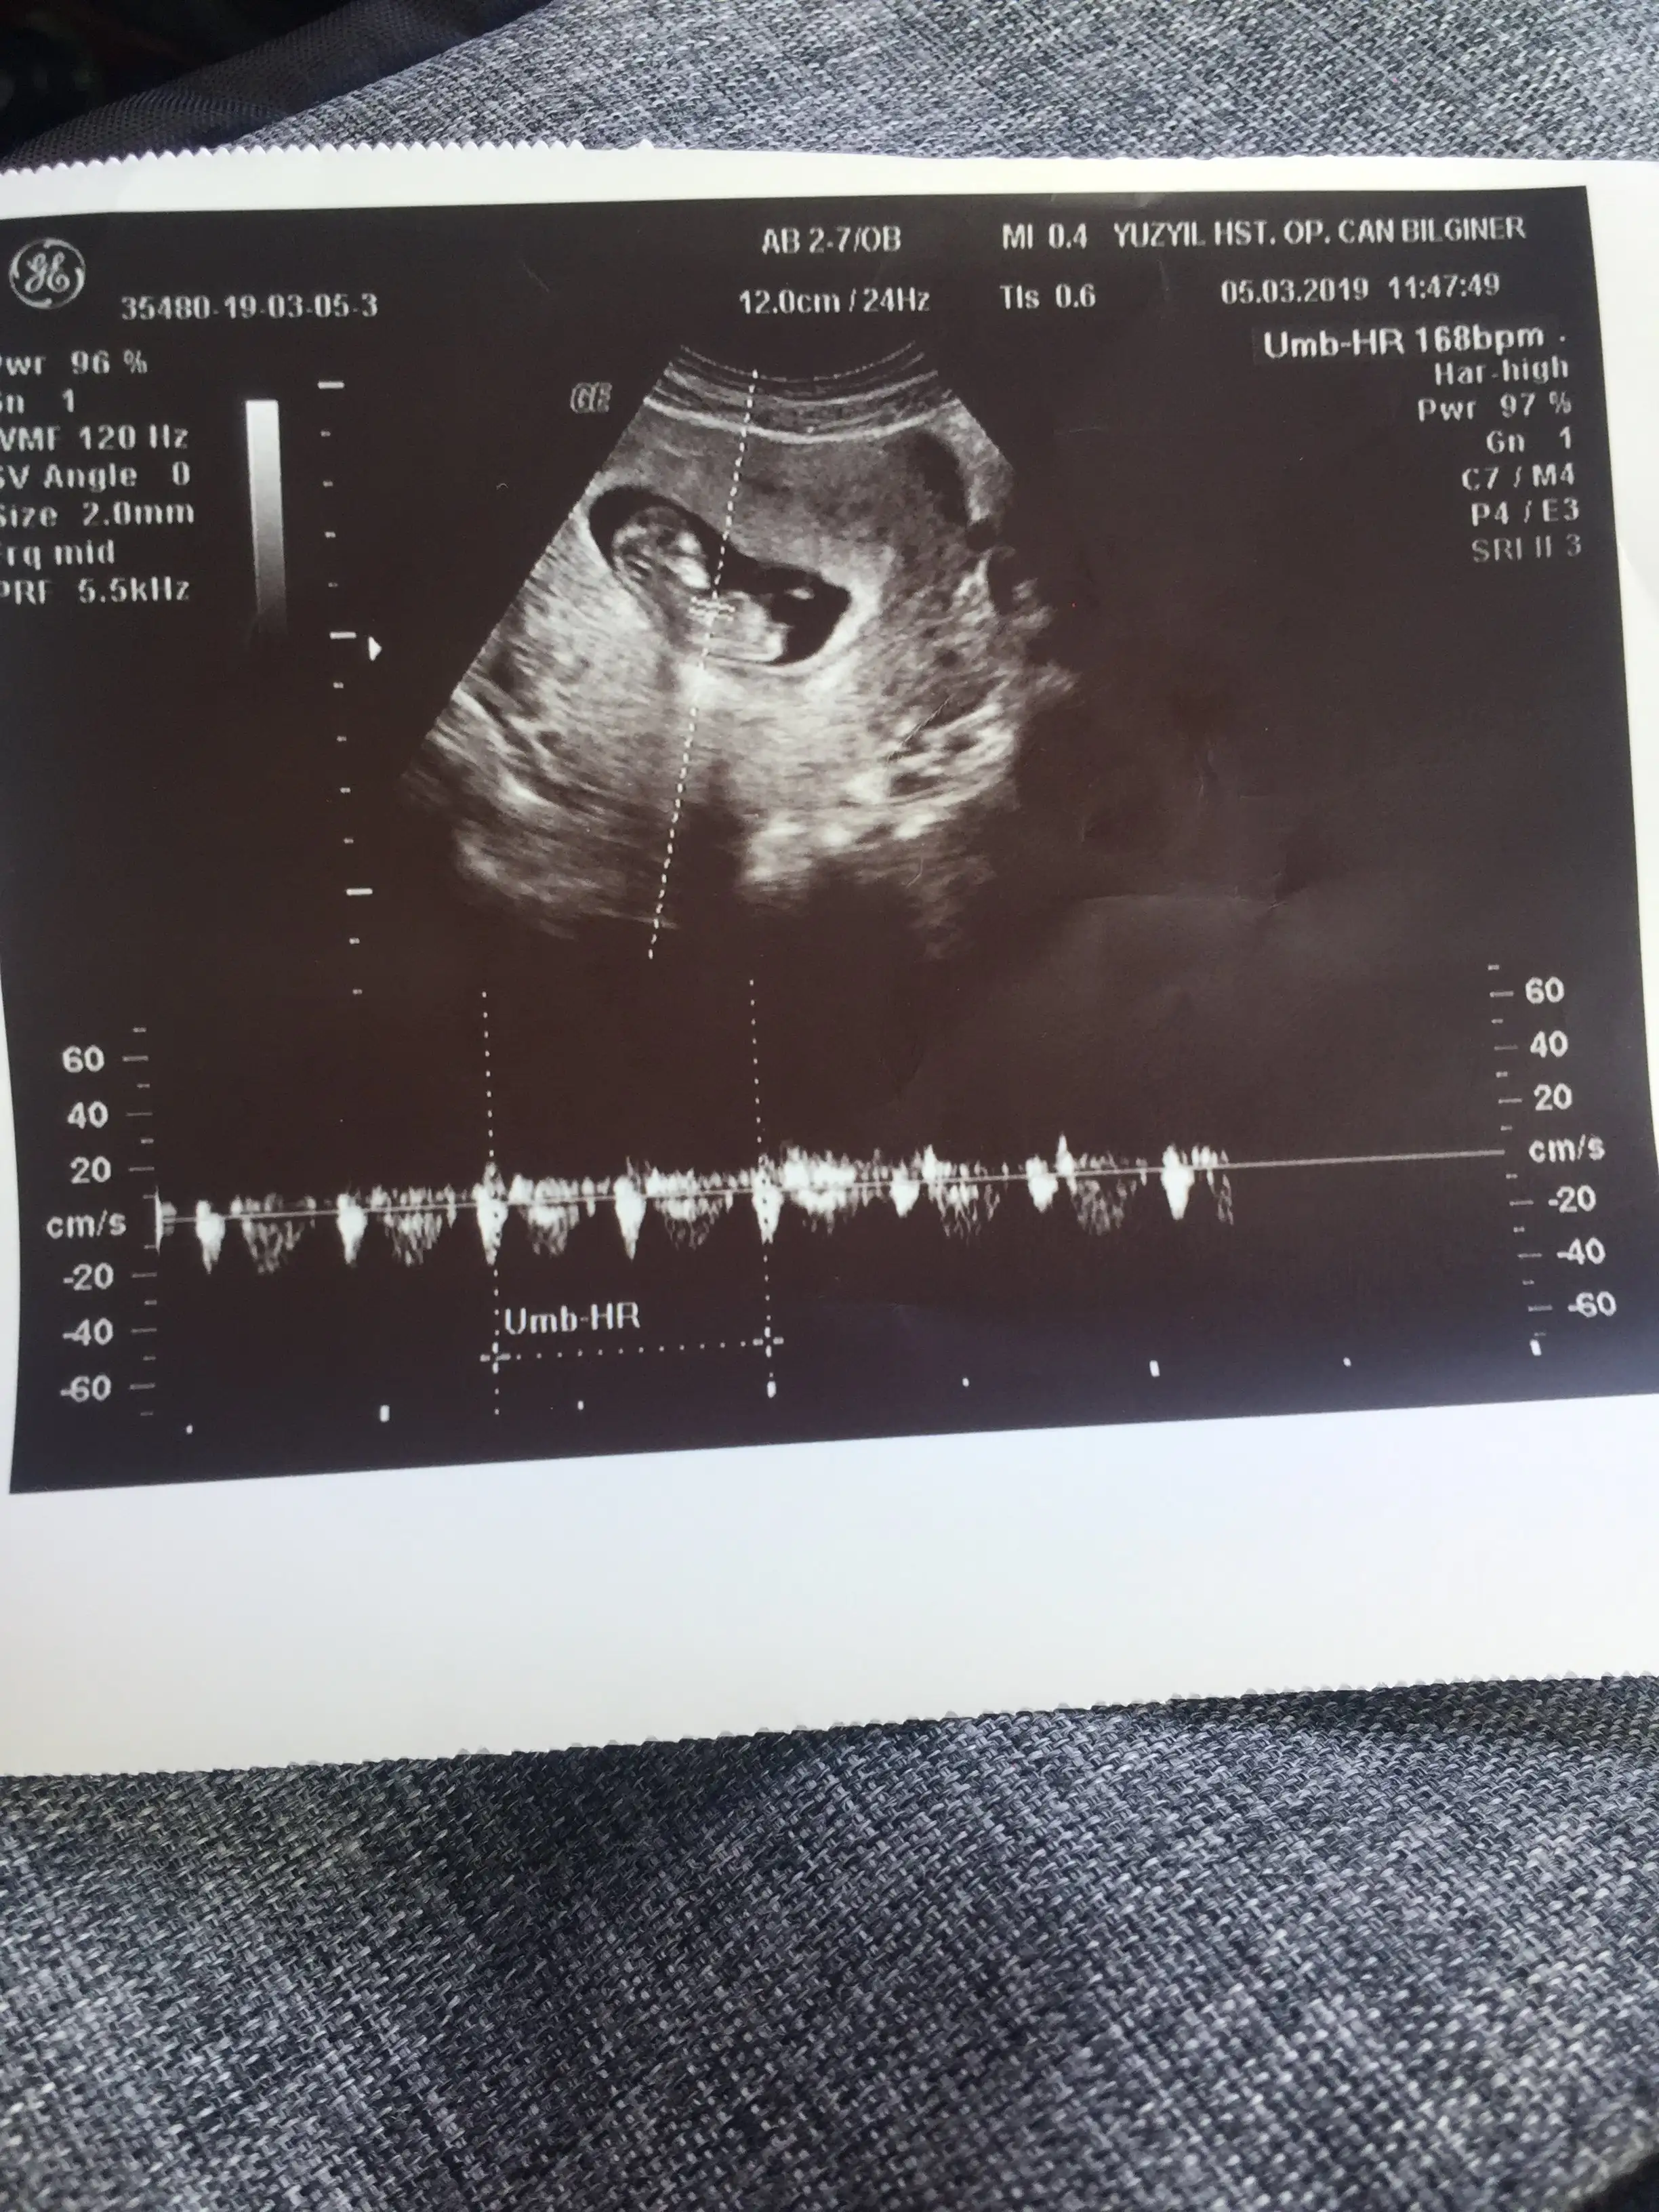

Erkek gibi hissettim canım hayırlısı olsunMerhaba, ilk ultrason alttan 5 haftalık , ikinci ultasonda karından 6+2 sizce cinsiyeti nedir ?

Sola tMerhaba, ilk ultrason 5 haftalık , ikinci ultasonda 6+2 sizce cinsiyeti nedir ?Eki Görüntüle 2245201 Eki Görüntüle 2245202

erkek gibi CanımMerhaba, ilk ultrason alttan 5 haftalık , ikinci ultasonda karından 6+2 sizce cinsiyeti nedir ?